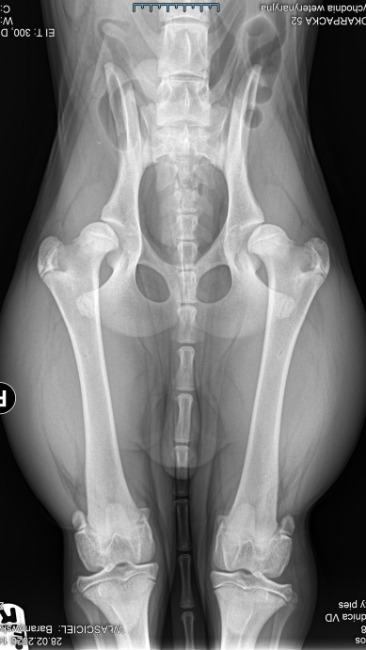

Zachowanie Kokosa nas niepokoiło, było czuć pod dłonią w miejscu opweiwwnym że coś się porusza. Szybkie RTG - złamanie główki kości udowej.. Z niczyjej winy - ryzyko, powikłanie po zabiegu 😭 (miejsce gdzie widoczna jest myszka komputerowa).